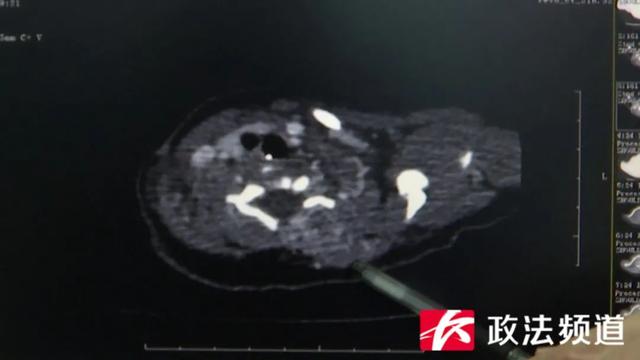

CT影像

医生表示,入院检查发现该患儿有血小板减低、溶血性贫血及凝血功能障碍,多次行输血小板及相关治疗效果欠佳,经多学科会诊,患儿确诊为卡梅综合征,又称巨大血管瘤-血小板减少综合征。“孩子出生时就有了,随着年龄的增大,瘤体如果没有得到治疗的话,瘤体会不断消耗血液里的血小板,就会导致凝血功能障碍。”黄文雅表示。在新生儿四科及麻醉手术科的支持下,血管介入科尽快为该患儿安排了微创介入手术,术后造影显示,“肿瘤染色血管区”明显缩小、变浅,病变主要供血血管被栓塞,手术很成功。医生介绍,患儿术后恢复良好,术后血小板及凝血功能明显升高且持续稳定、病灶颜色逐渐变浅、质地变软、无破溃出血。“家长要注意观察小孩身上有没有鼓起,有没有疤,另外观察皮下有没有出血点,如果发现了及时来就诊,早期诊断早期治疗疗效是非常好的。”医生提醒广大家长。